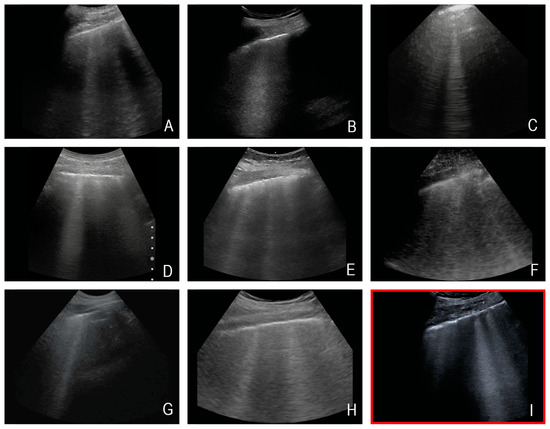

2.5. The Sonographic Questions

| No. | Organ | Sonographic Question | Sonographic Section | Near vs. Far Field | Penetration Depth |

|---|---|---|---|---|---|

| 1. | Inferior Vena Cava (IVC) | Diameter and variability of IVC, volume status | Median sagital section | Far field | up to 12 cm |

| 2. | Pleural effusion | Presence of effusion | Flank section | Far field | up to 12 cm |

| 3. | Needletracking | Visibility of the needle | Variable: abdomen or intercostal | Near field | up to 6 cm |

| 4. | B-Lines | Presence and number | Thoracic, intercostal | Near field | up to 4 cm |

| 5. | Gallbladder | Wall thickening, sludge, oedema, stones | Diagonal section—right upper abdomen | Near/middle field | up to 8 cm |